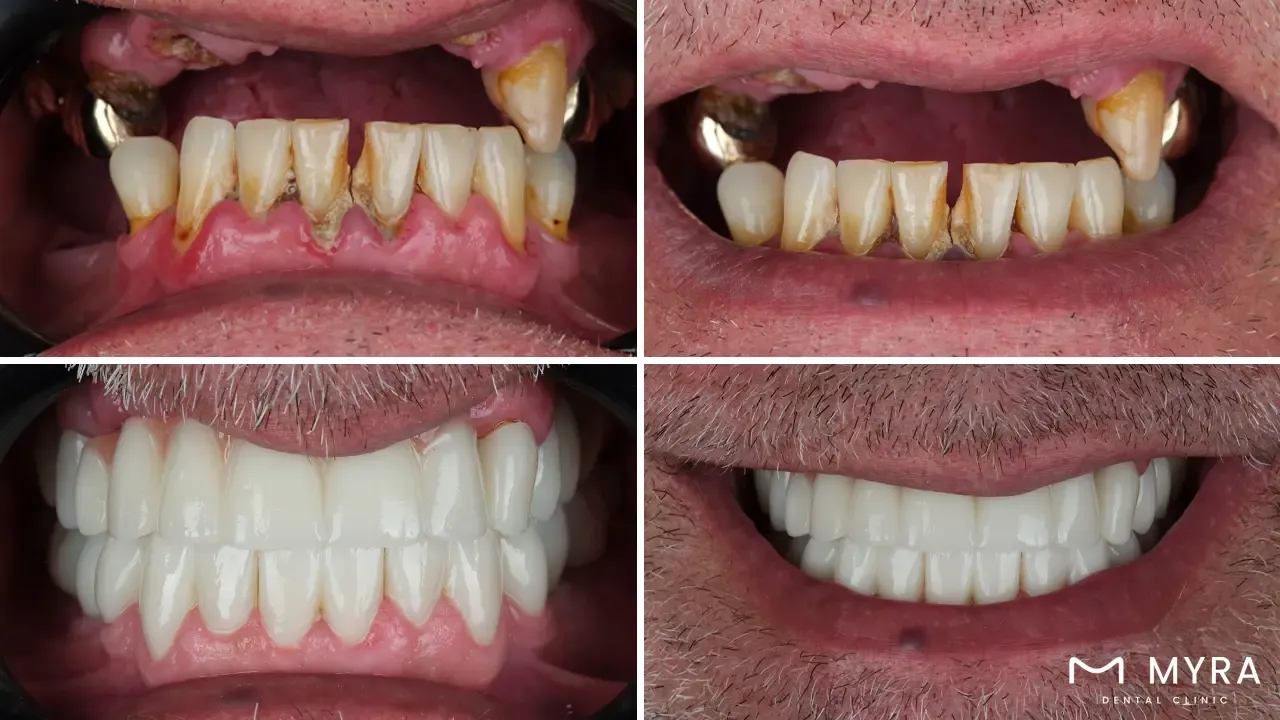

The Immediate Load Dental Implant is a kind of oral device which is viable to be inserted in either the upper or lower jawline or both, in just a short span of time. It is primarily implanted through a process called immediate loading which is normally completed within 48 hours. Immediate loading is a procedure for implant placement which involves placing the prosthesis on top of the loaded implant, restoring a person’s ability to properly chew food, smile, and speak. The prosthesis is most often fitted from a patient’s tooth within the day the implant is placed, which makes the process absolutely swift.

One of the best benefits of an immediate load dental implant is its capability to provide rapid results. Patients are able to utilize and cherish their newly restored teeth without having to endure several months of waiting for the procedure to be finished. Some of the other benefits which the procedure is able to usher includes providing a more effective technique for creating soft-tissue at the single-tooth repair site, promoting effective final restoration fabrication, and reducing early crestal bone loss achieved through countersinking the implant beneath the crestal bone.

Immediate Load Dental Implant, from the word itself, simply implies a quick placement of oral devices. The process involved in immediate load dental implantation, called immediate loading is known for its swift outcome. Immediate loading takes up to 48 hours or less to be completed, unlike other esthetic dental procedures which takes several months to finish. Immediate load dental implants are sometimes called “same day smile” or “teeth in a day” since it is able to provide teeth restoration in just a single session.

Lastly, immediate load implants contribute to enhanced patient satisfaction. The possibility of immediately replacing missing or failing teeth and avoiding prolonged healing periods is a compelling reason why patients opt for this method. The quicker restoration process leads to increased patient satisfaction. The treatment causes less pain, eliminates the need for interim dentures, and results in more aesthetically pleasing tooth restorations. In a scenario where a patient needs a front tooth replaced, the entire implant procedure can be completed in just a day or two, instantly improving their appearance and reducing the inconvenience of multiple appointments and recovery periods.